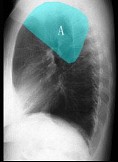

- 单项选择题如图所示正常胸部X线影像图像上,该英文字母所代表的肺段为 ( )

A、尖段

B、后段

C、尖后段

D、舌叶上段

E、前段